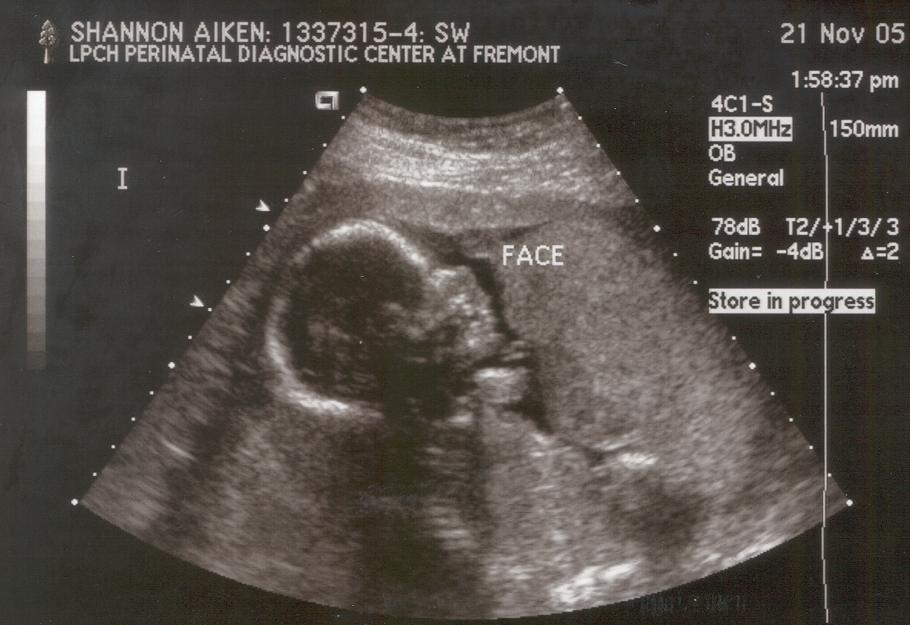

20 weeks: